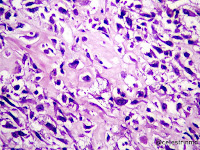

MICROSCOPIC IMAGES:

sheets of atypical large, epithelial-like cells.

Eosinophylic osteoid formation between the tumour cells.

Osteoid formation with calcification.

prominent vascular invasion.

Epitheliod-like tumour cells.

FOCAL chondroblastic differentiation.

- Neoplastic cells: marked atypia (pleomorphic, hyperchromatic)

- Multiple cell morphologies often present in one tumor (epithelioid, plasmacytoid, spindled, small round cells, clear cells, giant tumor cells)

- Neoplastic bone (necessary for diagnosis): no minimum quantity necessary

- Most common: filigree / lace-like disorganized woven bone (intimately associated with neoplastic cells)